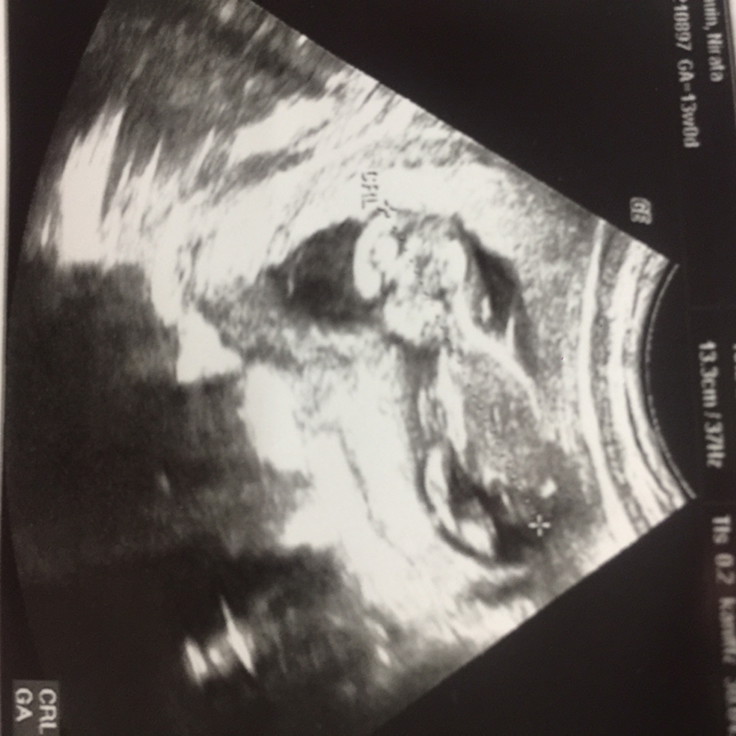

13 weeks